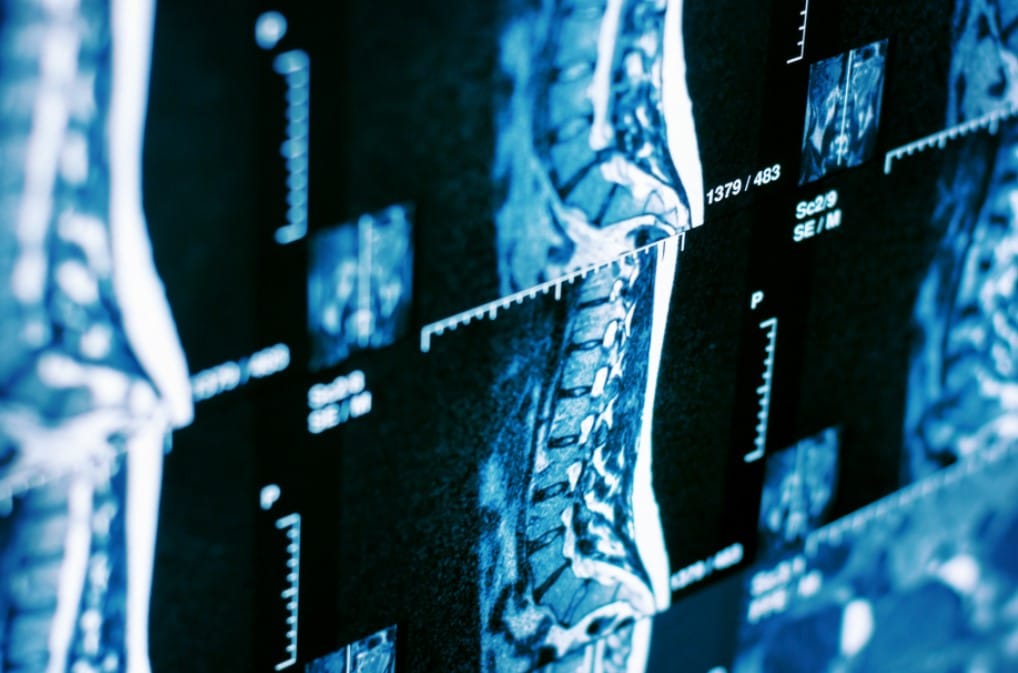

Para detectar la causa real, uno de los exámenes más precisos y completos es la resonancia magnética de columna, una herramienta clave que permite observar en detalle las estructuras internas sin necesidad de radiación ni procedimientos invasivos.

La resonancia magnética (RM) es un examen médico avanzado que utiliza campos magnéticos y ondas de radio para obtener imágenes detalladas del interior del cuerpo.

Tras el examen, las imágenes son revisadas por especialistas en diagnóstico por imágenes, quienes emiten un informe detallado para tu médico tratante.